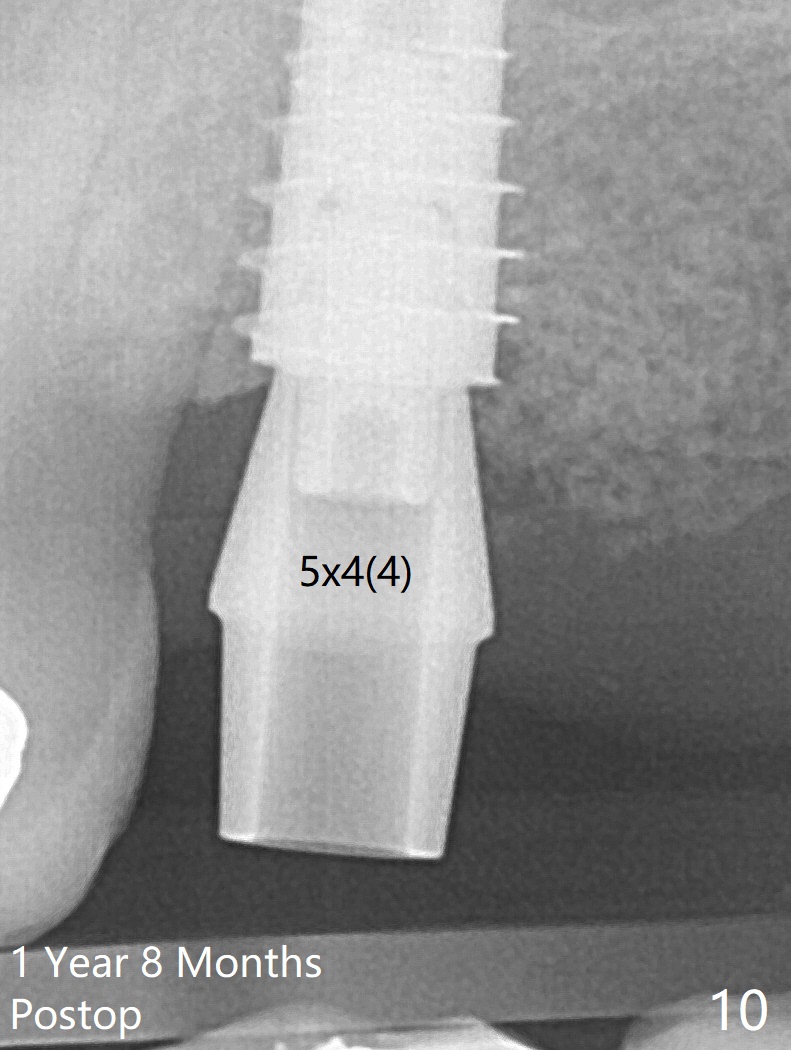

The 3 remaining sockets (Fig.1 *) around the final implant are filled with sticky bone (Fig.2 *).  The sockets are non-existing 1 year 7 months and 8 months postop (Fig.6,7 (BW)).